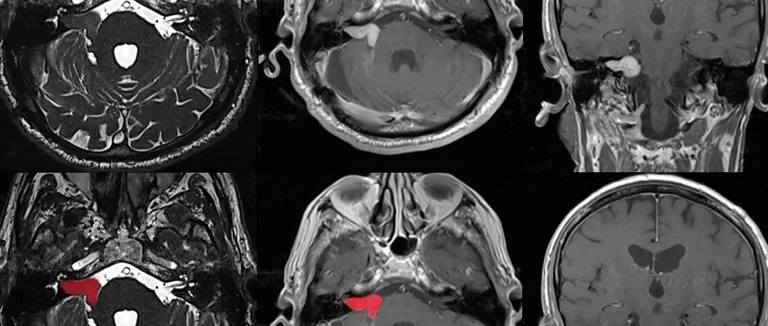

Le Brain Cancer Scan: Méthodes d'Imagerie Essentielles

Pour trouver les tumeurs cérébrales, les médecins utilisent des méthodes d'imagerie importantes. Ces techniques aident à trouver les tumeurs, à savoir leur type et leur impact sur le cerveau.

L'IRM (Imagerie par Résonance Magnétique)

L'IRM est très efficace pour explorer le cerveau et la moelle épinière. Elle fournit des images précises pour repérer les tumeurs.

La tomodensitométrie (TDM/Scanner)

La tomodensitométrie est une technique d'imagerie courante pour les tumeurs cérébrales. Elle est très utile en cas d'urgence.

La tomographie par émission de positons (TEP)

La TEP est une méthode d'imagerie fonctionnelle. Elle évalue l'activité métabolique des tumeurs cérébrales. Elle est souvent combinée avec l'IRM ou le TDM.